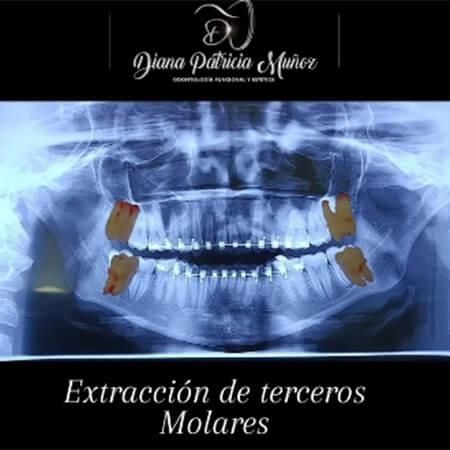

In my practice, I offer general and cosmetic dentistry, endodontics, periodontics, orthodontics, oral rehabilitation, smile design, and management of temporomandibular disorders such as bruxism, among other treatments. My commitment is to provide each patient with a personalized and comprehensive ca…

Before and After Gallery